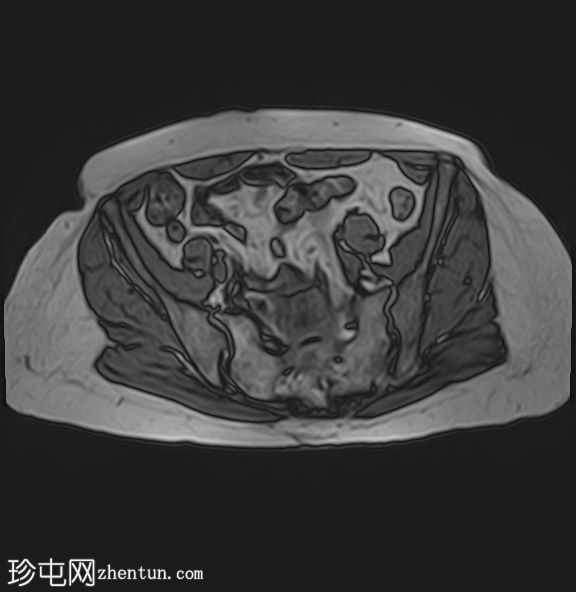

MRI

轴位T1加权像

(同相/反相)

轴位

T1加权像

脂肪抑制像

左侧肾上腺可见一边界清晰的病灶,大小约为3.0 × 2.4 × 2.0 cm。

化学位移成像显示,反相图像的信号强度较同相图像明显降低,与细胞内脂质含量相符。

右肾先天性缺失。左肾轻度肥大,信号强度正常。

肾上腺腺瘤的典型表现,反相成像可见明显的信号丢失。